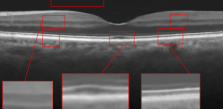

The proposed algorithm has been also tested for the super-resolution of the two other datasets. For dataset2, the middle slices of several 3D image have been selected for test and averaged with 2 previous and 2 next slices. The weights ’s set equal to for each B-scan. For the proposed approach, the patch sizes were set equal to 5 and 7 or (5 and 10) with window size equal to [2,2]. For MDT the window size was set to [2,2]. The results for the super-resolution of artificially missed B-scans of dataset2 with missing ratio have been illustrated in Fig. 6. Since this dataset does not contain reference images, PSNR and SSIM could not be reported. Hence, only visual comparison and the resulting CNR’s, with the following definition, have been reported for each algorithm:

| (14) |

where and are the mean and standard deviation of the foreground respectively and and are the mean and standard deviation of the background region, respectively. Averaged CNR’s for 5 Regions Of Interest (ROI) in each image (relative to an ROI selected in the background region of the image) have been computed. Note that ROI’s have been shown with red boxes in each image of Fig. 6. As the results show, the proposed algorithm results in a better output and higher CNR comparing to the other algorithms.